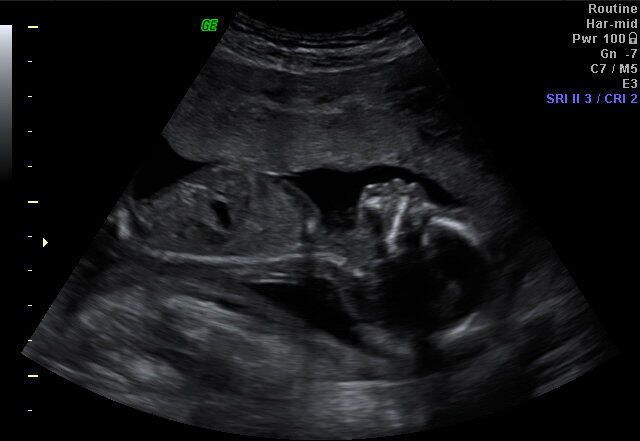

התיעוד הראשון מהיהריון הראשון, הרגע שבו בישרו לנו שיש לנו בן. למה השכנים החרדים שלי לא חיים עם החרדה התמידית שנולדת ברגע הזה?

2 לעתים המנגנון הזה עובד בכיוון ההפוך. כשאשתי היתה בהיריון הראשון הלכנו לבדיקת שקיפות עורפית. היא היתה בשבוע 13, והעובר היה באורך 8 ס"מ בערך, ושקל משהו כמו 30 גרם. קטן קטן קטן, אבל מספיק כדי שהטכנאית תבשר שיש לנו בן. ברגע שהיא אמרה את זה המחשבות שלי דילגו 18 שנה קדימה, ומיד חשבתי על הגיוס שלו. ממש לפני תחילת המלחמה עם איראן מלאו לבן הזה 16 שנה, ואני יודע שזה אומר שהוא תכף יקבל צו ראשון.